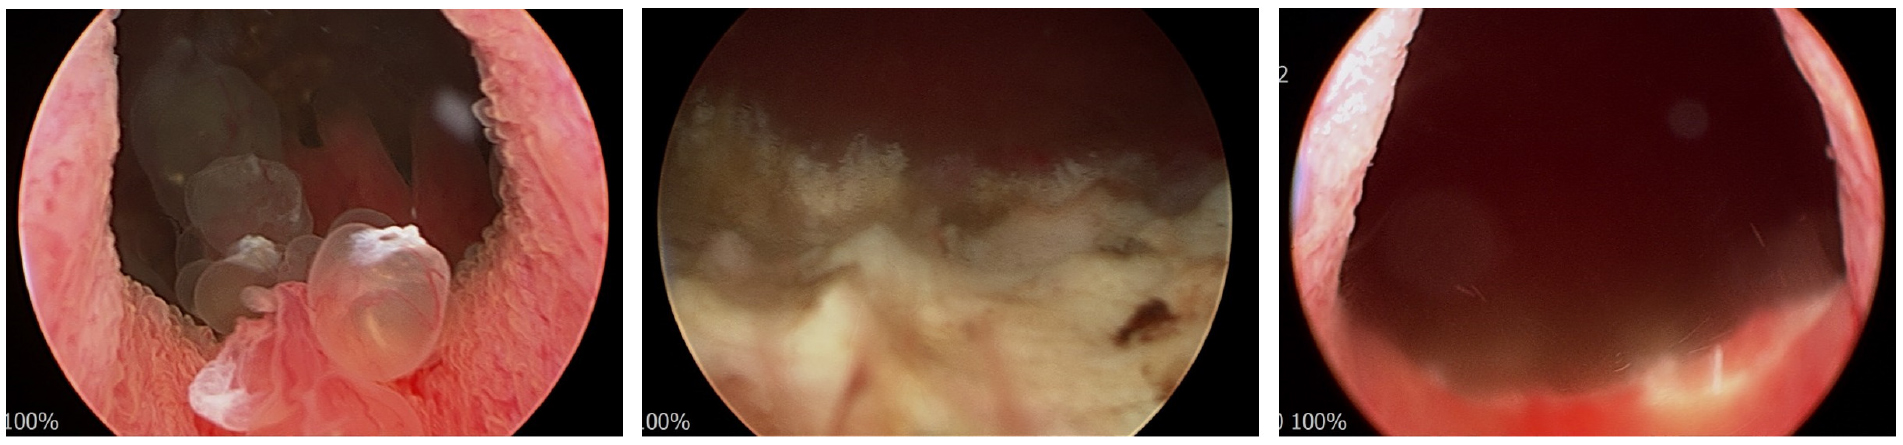

2.2. 수술적 치료; 경요도 방광 종양 절제술

척수마취 하 경요도 방광 종양 절제술(transurethral resection of bladder tumor)을 시행하였다. 방광목부터 삼각부(trigone)로 papillary mass를 cutting current (loop)를 사용하여 절제하였으며, 양측 요관구가 잘 관찰되지 않아 불필요한 cauterization을 주의하였다. 병변을 충분히 절제하여 방광목에 check valve로 작용하는 polypoid mass가 보이지 않고 방광목이 잘 열려 있는 것을 확인하였다.